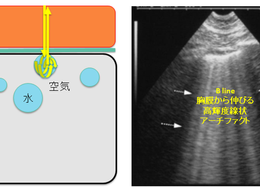

在宅医療で活用される肺エコーによる肺炎診断

在宅医療の現場では、X線やCTといった画像診断がすぐに使えない場面も多くあります。そんなとき、**肺エコー(Lung Ultrasound/LUS)**が大きな力を発揮します。特に、 通院困難な高齢者や寝たきりの方 において、肺炎による呼吸苦や発熱の鑑別に有効です。 🔍...

5月4日読了時間: 3分